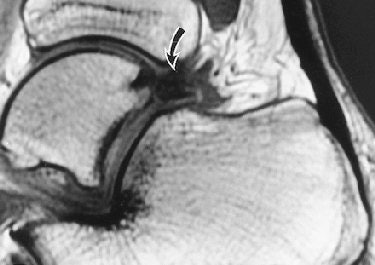

On the MRI exams in the U.K. study, Dr. Philip Robinson from Leeds Teaching Hospitals at St. James University Hospital in Leeds found a preponderance of posterolateral synovitis, thickened posterior talofibular ligaments, and a lack of FHL tenosynovitis

In a study published earlier this year by Robinson, the MR sequence consisted of axial proton density-weighted, sagittal T1-weighted conventional spin-echo imaging; axial, sagittal, and coronal T2-weighted conventional spin-echo fat-suppressed imaging; and gadolinium-enhanced axial and sagittal T1-weighted conventional spin-echo fat-suppressed imaging.

These exams were conducted in a patient population of nine athletes imaged on a 1.5-tesla scanner (Intera, Philips Medical Systems, Andover, MA). On imaging, the posterior ankle was evaluated for synovitis in the posteromedial, posterior, and posterolateral areas.

MR findings included posteromedial capsular thickening, tendon displacement, and posteromedial synovitis in all athletes with posteromedial impingement. Also, all posterolateral athletes had moderate to severe posterolateral synovitis. Bone marrow edema was prevent, but without specific distribution (Skeletal Radiology, February 2006, Vol. 35:2, pp. 88-94).

The focus of Robinson's most recent study, conducted with Dr. Steve Bollen from Bradford Royal Infirmary in Bradford, UK., was sonographically guided injection therapy. "We believe MRI should always be performed before injection to prevent subsequent masking of significant concomitant osteochondral or ligamentous injury," they wrote. "Our study results show a role for sonographically guided steroid and anesthetic injection into the posterolateral capsule abnormality" (American Journal of Roentgenology, July 2006, Vol. 187, pp. W53-W58).

| A 30-year-old male soccer player with clinical posterior impingement. Sagittal T2-weighted fat-suppressed MR image (TR/TE, 3,242/90; echo-train length, 9) shows os trigonum (lower arrow), joint effusion, and nodular posterolateral synovitis (arrowheads) between os trigonum and edematous posterior tibia (upper arrow). |